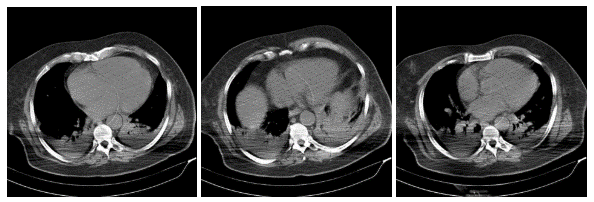

Solving Image-Based Medical 3D Printing Challenges

Medical 3D printing is becoming increasingly valuable for manufacturers and clinicians to solve patient-specific problems through tailored implants to improve diagnostic decision-making.